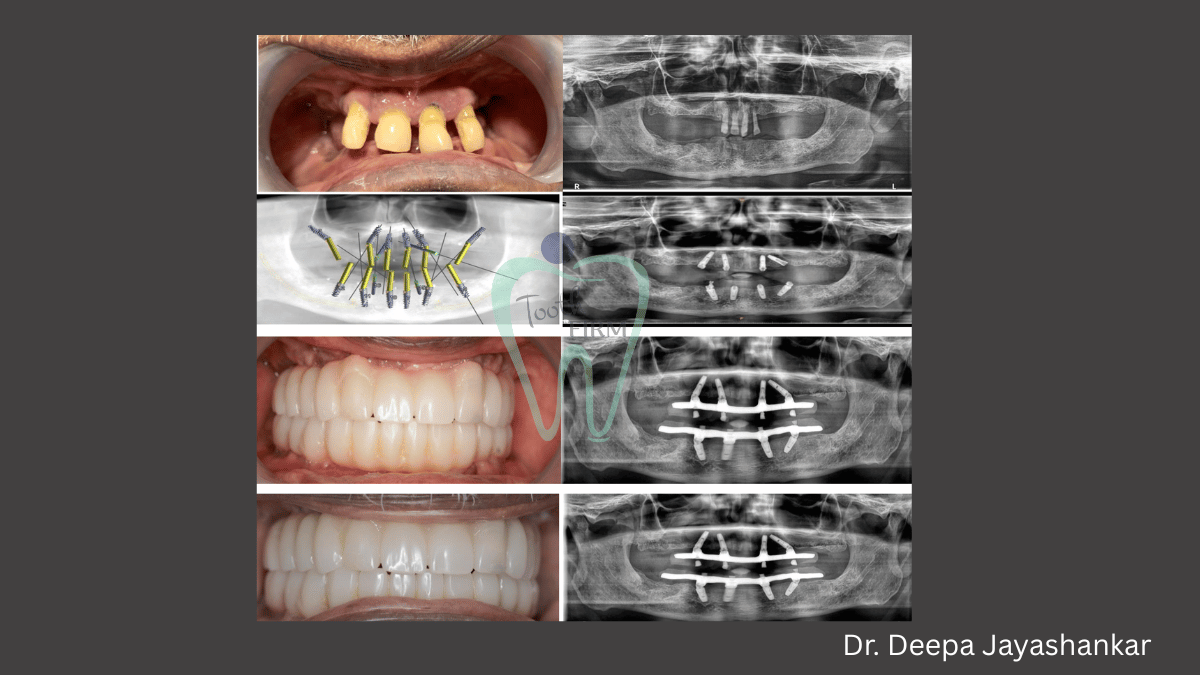

Full Mouth Rehabilitation

Full Mouth Rehabilitation with Smile Designing